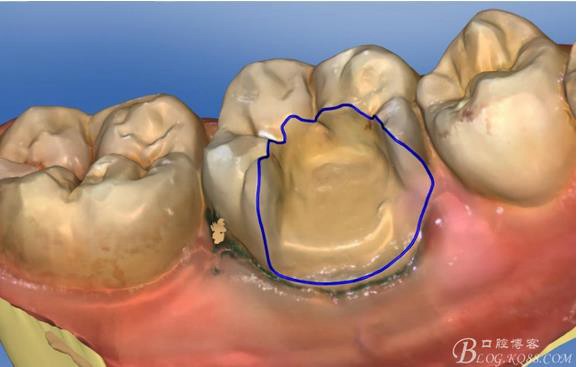

畫線是最關鍵的,線畫不好制出的修復體會出現(xiàn)邊緣缺損 或多 或少,醫(yī)生和技術(shù)配合

掃描 畫線 準備研磨